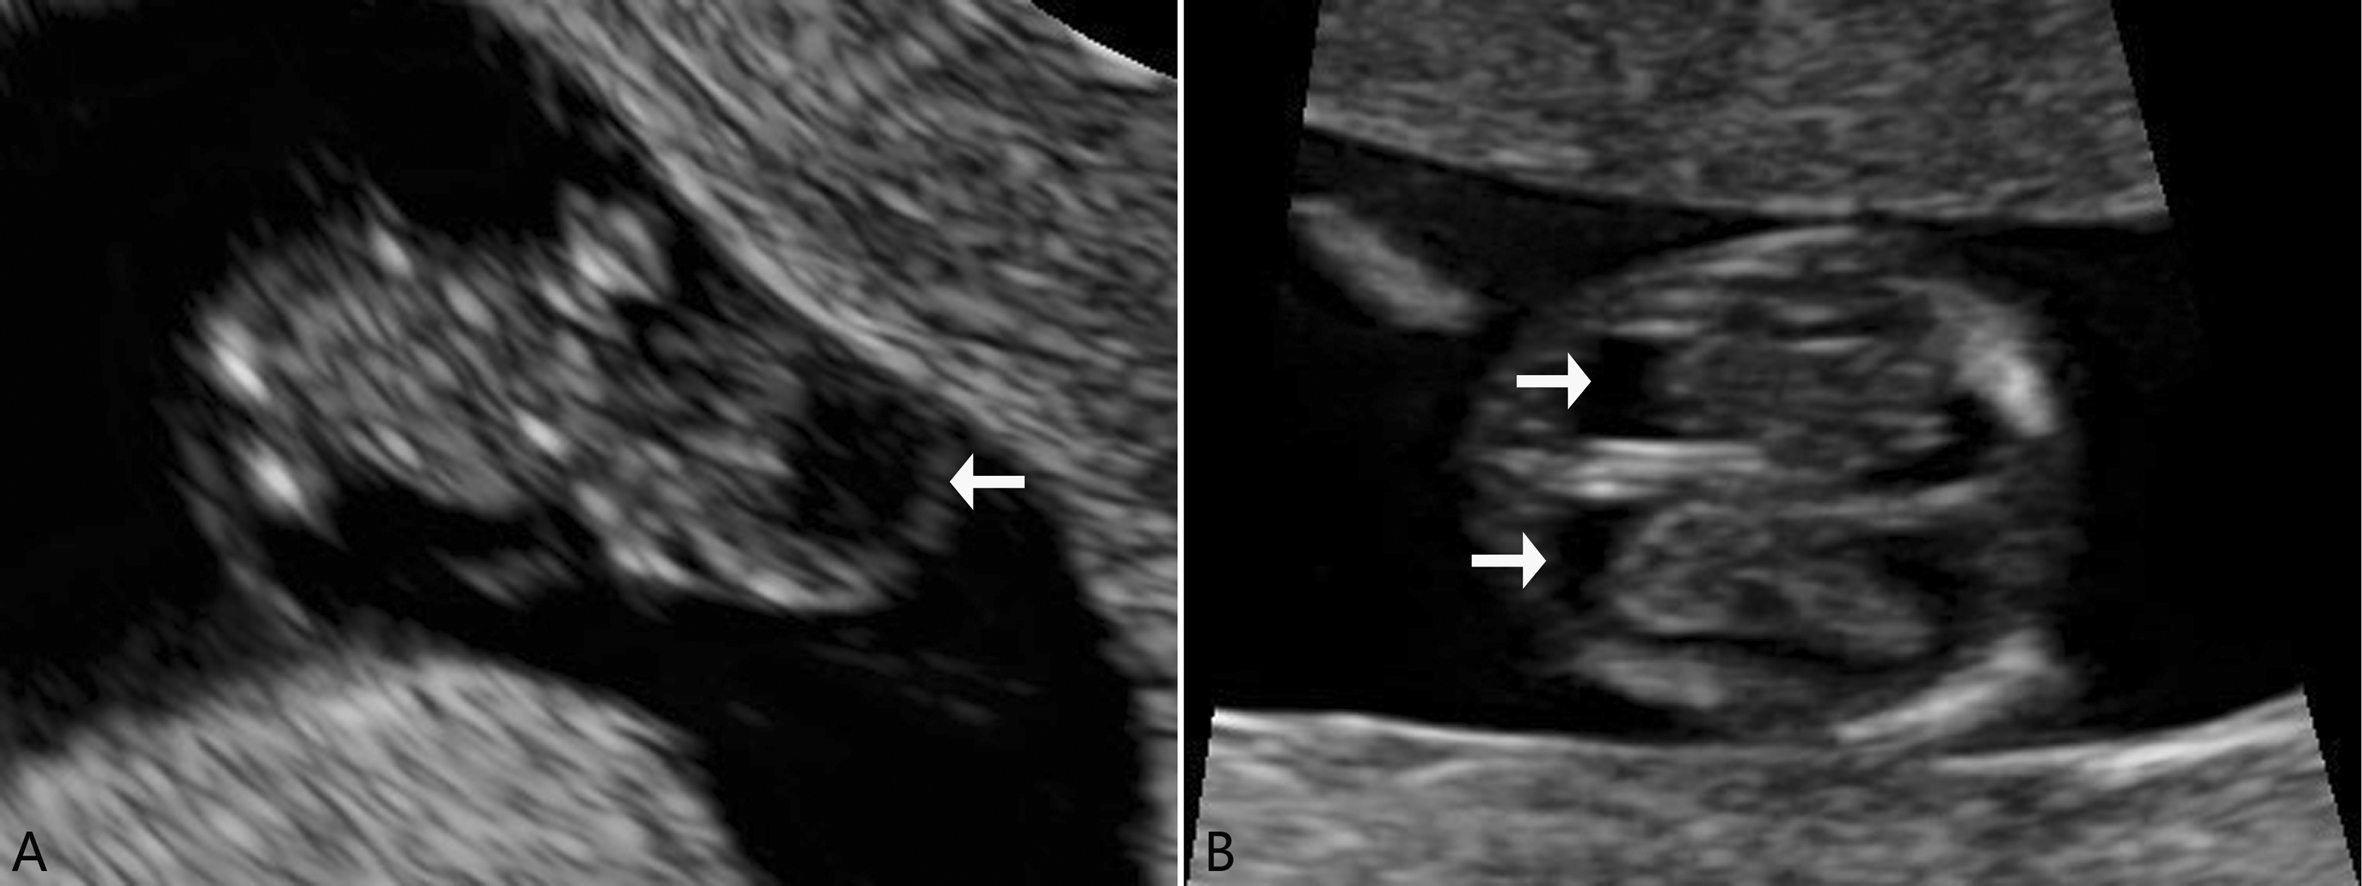

图1 7周妊娠胎头的脑泡回声(A)及11周妊娠的脉络丛强回声(B)

1.头颅横断面 显示完整的颅骨形态,头颅呈椭圆形,脑中线清晰可见,双侧脑半球对称,看似增宽的双侧侧脑室(图2A),内充满高回声的脉络膜。向颅底方向倾斜探头,可以看到小脑半球(图2B)。

图2 早孕期胎头声像图(箭头之间为小脑)

2.头颅正中矢状切 显示面部轮廓:鼻骨,额头,下颌,颅内可以看到第三脑室,呈高回声等号形态的第四脑室。